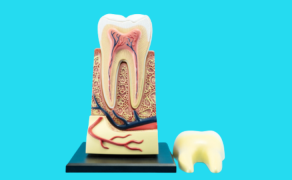

Obliteracja jamy zęba – postępowanie kliniczne

- Czym jest obliteracja?

- Jak leczyć endodontycznie zęby z obliteracją?

- Przedstawiono postępowanie kliniczne pozwalające na przeprowadzenie skutecznego leczenia kanałowego zęba z obliteracją jamy zęba. Na podstawie przypadków.

Wprowadzenie. Obliteracja jest procesem, w wyniku którego dochodzi do zmniejszania jamy zęba w następstwie odkładania związków mineralnych wzdłuż ścian kanału korzeniowego lub w wyniku działania bodźców zewnętrznych, takich jak próchnica lub urazy zębów. Leczenie endodontyczne zębów z obliteracją jest zabiegiem trudnym. Niektórzy autorzy zalecają obserwację i podjęcie leczenia dopiero w sytuacji występowania objawów klinicznych lub zmian patologicznych widocznych na zdjęciach rentgenowskich. Cel pracy. W pracy przedstawiono postępowanie kliniczne pozwalające na przeprowadzenie skutecznego leczenia kanałowego zębów z obliteracją jamy zęba. Podsumowanie. Opracowanie zobliterowanej jamy zęba jest zabiegiem trudnym, wymagającym dokładnej znajomości morfologii systemu kanałowego, umiejętności i zdolności manualnych klinicysty oraz odpowiedniego sprzętu i urządzeń powiększających.

Introduction. Obliteration of the pulp cavity is a process resulting in the reduction of the pulp cavity following the deposition of mineral compounds along the walls of the root [...]